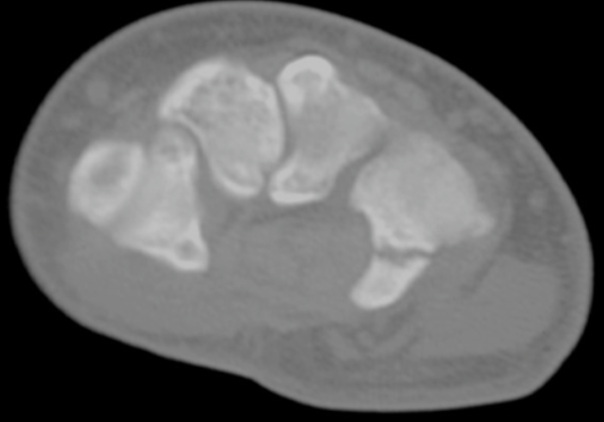

- CT Scan

- less effective than bone scan/ MRI

- Useful for location of ffracture and progression of nonunion/union post surgery